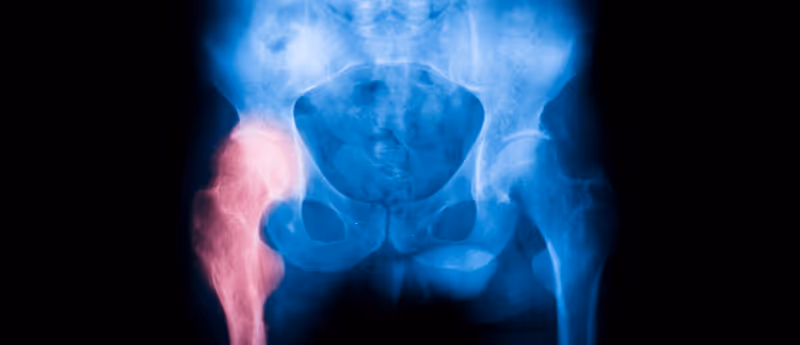

Developing a machine learning tool to help the most vulnerable following a hip fracture

Researchers have trained a machine learning tool to identify those at greatest risk of mortality in the year following a hip fracture using their age and features easily obtained from basic lab and blood tests. A machine learning tool that can accurately predict the risk of mortality within 1 year of a hip fracture has been successfully developed. This follows a retrospective study of almost 4,000 first-time hip fracture records from in-hospital database systems at Beth Israel Deaconess Medical Center (Boston, USA). This study identified age as the most significant predictor of mortality, followed by nine features that can be identified in basic blood and lab test data. These results could revolutionize hip fracture treatment and aftercare by helping to identify those at the highest risk of death following hip fracture, and who would benefit from a greater degree of medical intervention. The risk of hip fracture increases exponentially with age and can severely impact mobility and quality of life. Within a year of fracture, 20-30% of patients die, while 50% lose the ability to walk. Identifying those at greatest risk of deterioration is a key strategy to prevent loss of life and burden on healthcare services. In the study, different machine learning categorization models were trained to identify the risk of mortality following fracture in a training set of 3,000 patient records, taking into consideration 156 features. The vast majority of these features were from basic blood and lab test results, while some were demographic features such as age or marital status. Microsoft’s LightGBM machine learning framework was the most accurate model when predicting 1-year mortality based on these features, out of the ten machine learning categorization models tested. Following this training step, the LightGBM model was tested on a data set of 751 patient records, returning an accuracy of 81% when it assessed 1-year mortality prediction. The 156 features that contributed to this prediction were then ranked and compared. While age was decisively the most important feature, the next nine features were all biomarkers obtained from the blood and lab test results. These biomarkers included glucose and platelet count. When 1-year mortality prediction was based on just these ten most important features, the accuracy of the LightGBM model dropped by just 1%. This demonstrates that these ten features are sufficient enough alone in predicting 1-year mortality with a high degree of accuracy. Most of these features were also in the top ten features when predicting 5- and 10-year mortality with LightGBM models. “Our models show that certain biomarkers can be particularly useful in characterizing the risk of poor outcomes following hip fractures,” explained the corresponding author George Asrian (University of Pennsylvania; PA, USA). The results of this study demonstrate that machine learning tools can be used to spot patterns relevant to health that cannot be identified by humans alone and have the potential to greatly improve mortality after hip fracture.